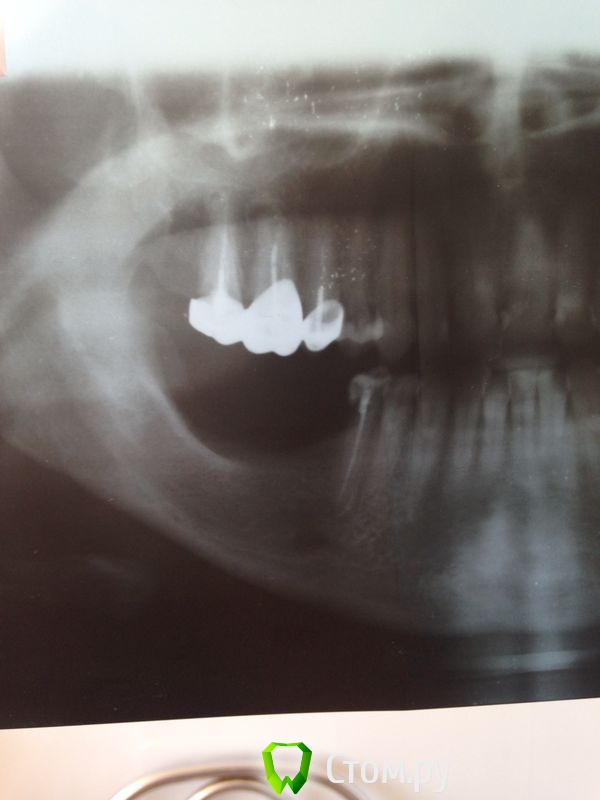

7Ольга777 Опубликовано 1 июля, 2014 Поделиться Опубликовано 1 июля, 2014 (изменено) Здравствуйте уважаемые врачи! Очень хочу попросить совета, что делать или не делать)? 21 июня мне поставили 3 импланта, пила 5 дней антибиотики, нимесил, мазала ,полоскала, все как положено. Беспокоила боль по ночам, боль в горле, ухе, лимфоденит появился на следующий день после установки. Пульсирующая вниз боль по ночам, помогал нимесил. Сняли швы,десна зажила, назначили нейровитан и компрессы с димексидом, все делаю, но все же вот на 10 день после установки боль сохраняется,не острая, но практически постояння, соседние зубы без проблем, болеть не могут, но почему то под ними все болит, больно дотрагиваться к косточке внизу подбородка, даже под здоровыми зубами. И ощущение от зубов на этой стороне, где импланты другое,как будто это не зубы, а пилоты, как будто они пластиковые.Небольшая боль в ухе, шее сохраняется. Тенденции к улучшению не замечаю с болью в кости внизу. Снимки до имплантации и после 7 дней после имплантации. Ощущение, что в кости нарыв под здоровыми зубами,которые идут от большого импланта,под нима все начинается и идет вниз((, возможно все нормально,так и должно быть. Если можно, скажите, пожалуйста. Врач ничего не говорит, советует пить нимесил. Спасибо Вам, если читаете!!!! Изменено 1 июля, 2014 пользователем 7Ольга777 Ссылка на комментарий

Bier Опубликовано 1 июля, 2014 Поделиться Опубликовано 1 июля, 2014 Зубы не пострадают. Длительные боли говорят о патологическом процессе, но имплантата 3 и не ясно от какого проблемы.Причин может быть много, патология на рентгене будет видна через 7-10 дней Ссылка на комментарий